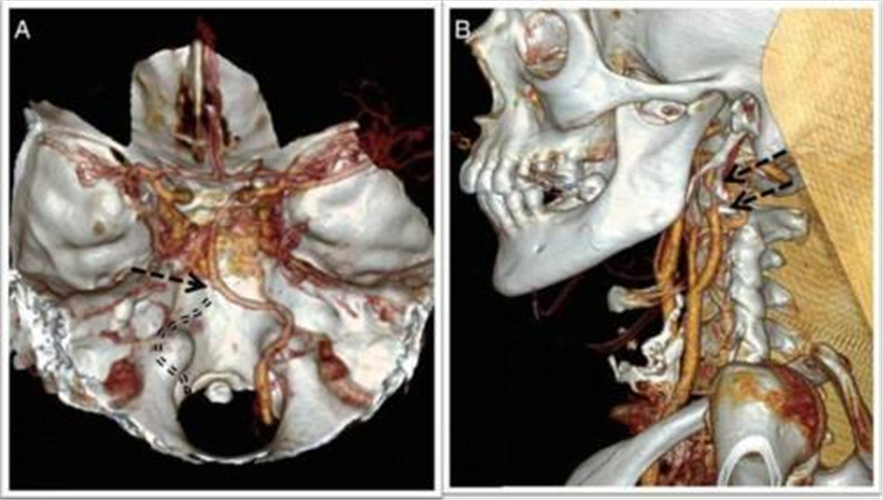

腦梗塞圖片

小腦腦梗塞組圖

小腦腦梗塞